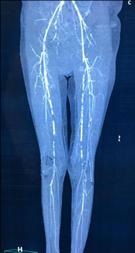

血管病变:主要影响中小动脉,导致血管硬化狭窄,甚至闭塞

▲ CTA:下肢动脉弥漫性钙化,闭塞